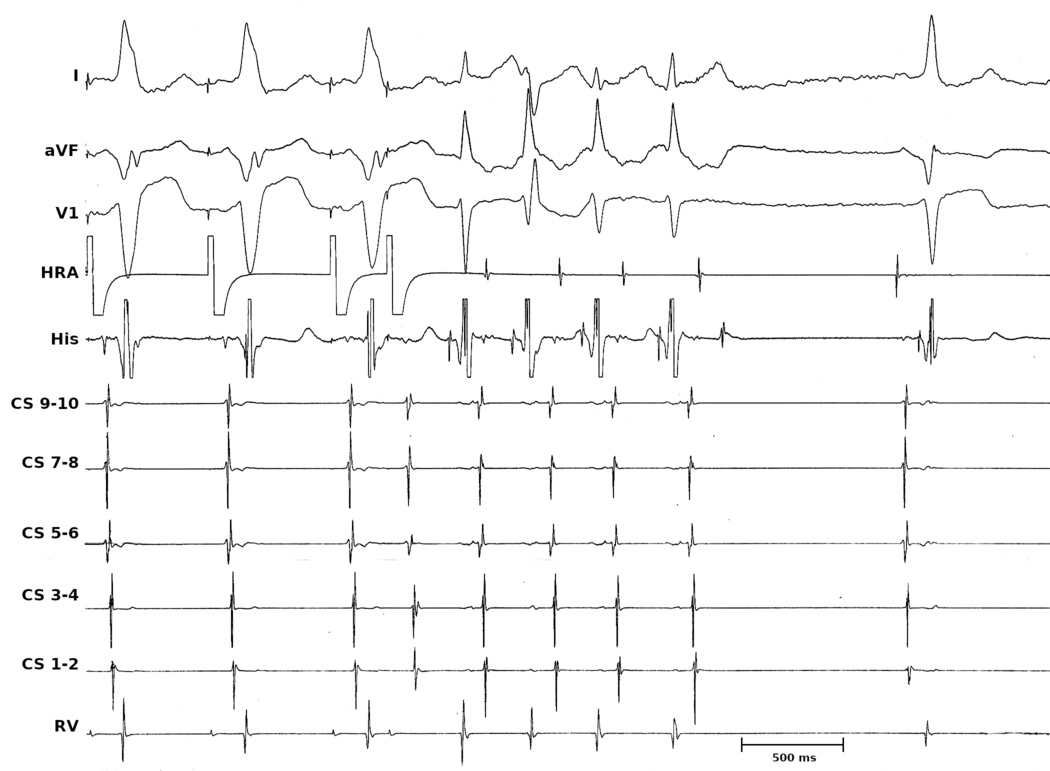

• What is the return response - VAV vs VAAV

• What is the cPPI-TCL ? (VAV)

• What is the SA-VA (VAV)

Tachycardia continues

vav_avnrt.jpg